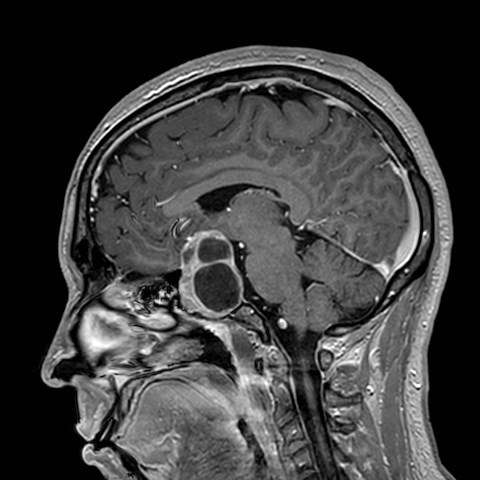

La resonancia magnética cerebral ha revelado que los adenomas hipofisarios están presentes en aproximadamente un 16% de la población general. Sin embargo, la gran mayoría de estos hallazgos corresponden a microadenomas, es decir, tumores menores de un centímetro de diámetro. Muchos de estos microadenomas no llegan a crecer lo suficiente como para producir síntomas por compresión local o disfunción hipofisaria, lo que contribuye a que permanezcan clínicamente silenciosos en muchos casos.

Imagenología

La resonancia magnética de hipófisis con contraste dinámico y en equipos de alta resolución (3 teslas) constituye la técnica de imagen de elección tanto para el diagnóstico inicial como para el seguimiento de los adenomas hipofisarios. Este tipo de resonancia permite una caracterización detallada del tamaño, extensión y relación del tumor con estructuras adyacentes, así como una evaluación precisa de posibles cambios en el tiempo.

En el caso de los microadenomas hipofisarios no funcionales menores de 0.5 centímetros, no se considera necesario un seguimiento por imagen, dado su escaso potencial de crecimiento o complicaciones. Sin embargo, cuando estos adenomas alcanzan o superan los 0.5 centímetros, se recomienda repetir la resonancia magnética a los seis meses, luego de forma anual durante tres años. Si no se observa crecimiento, el seguimiento puede hacerse con menor frecuencia.